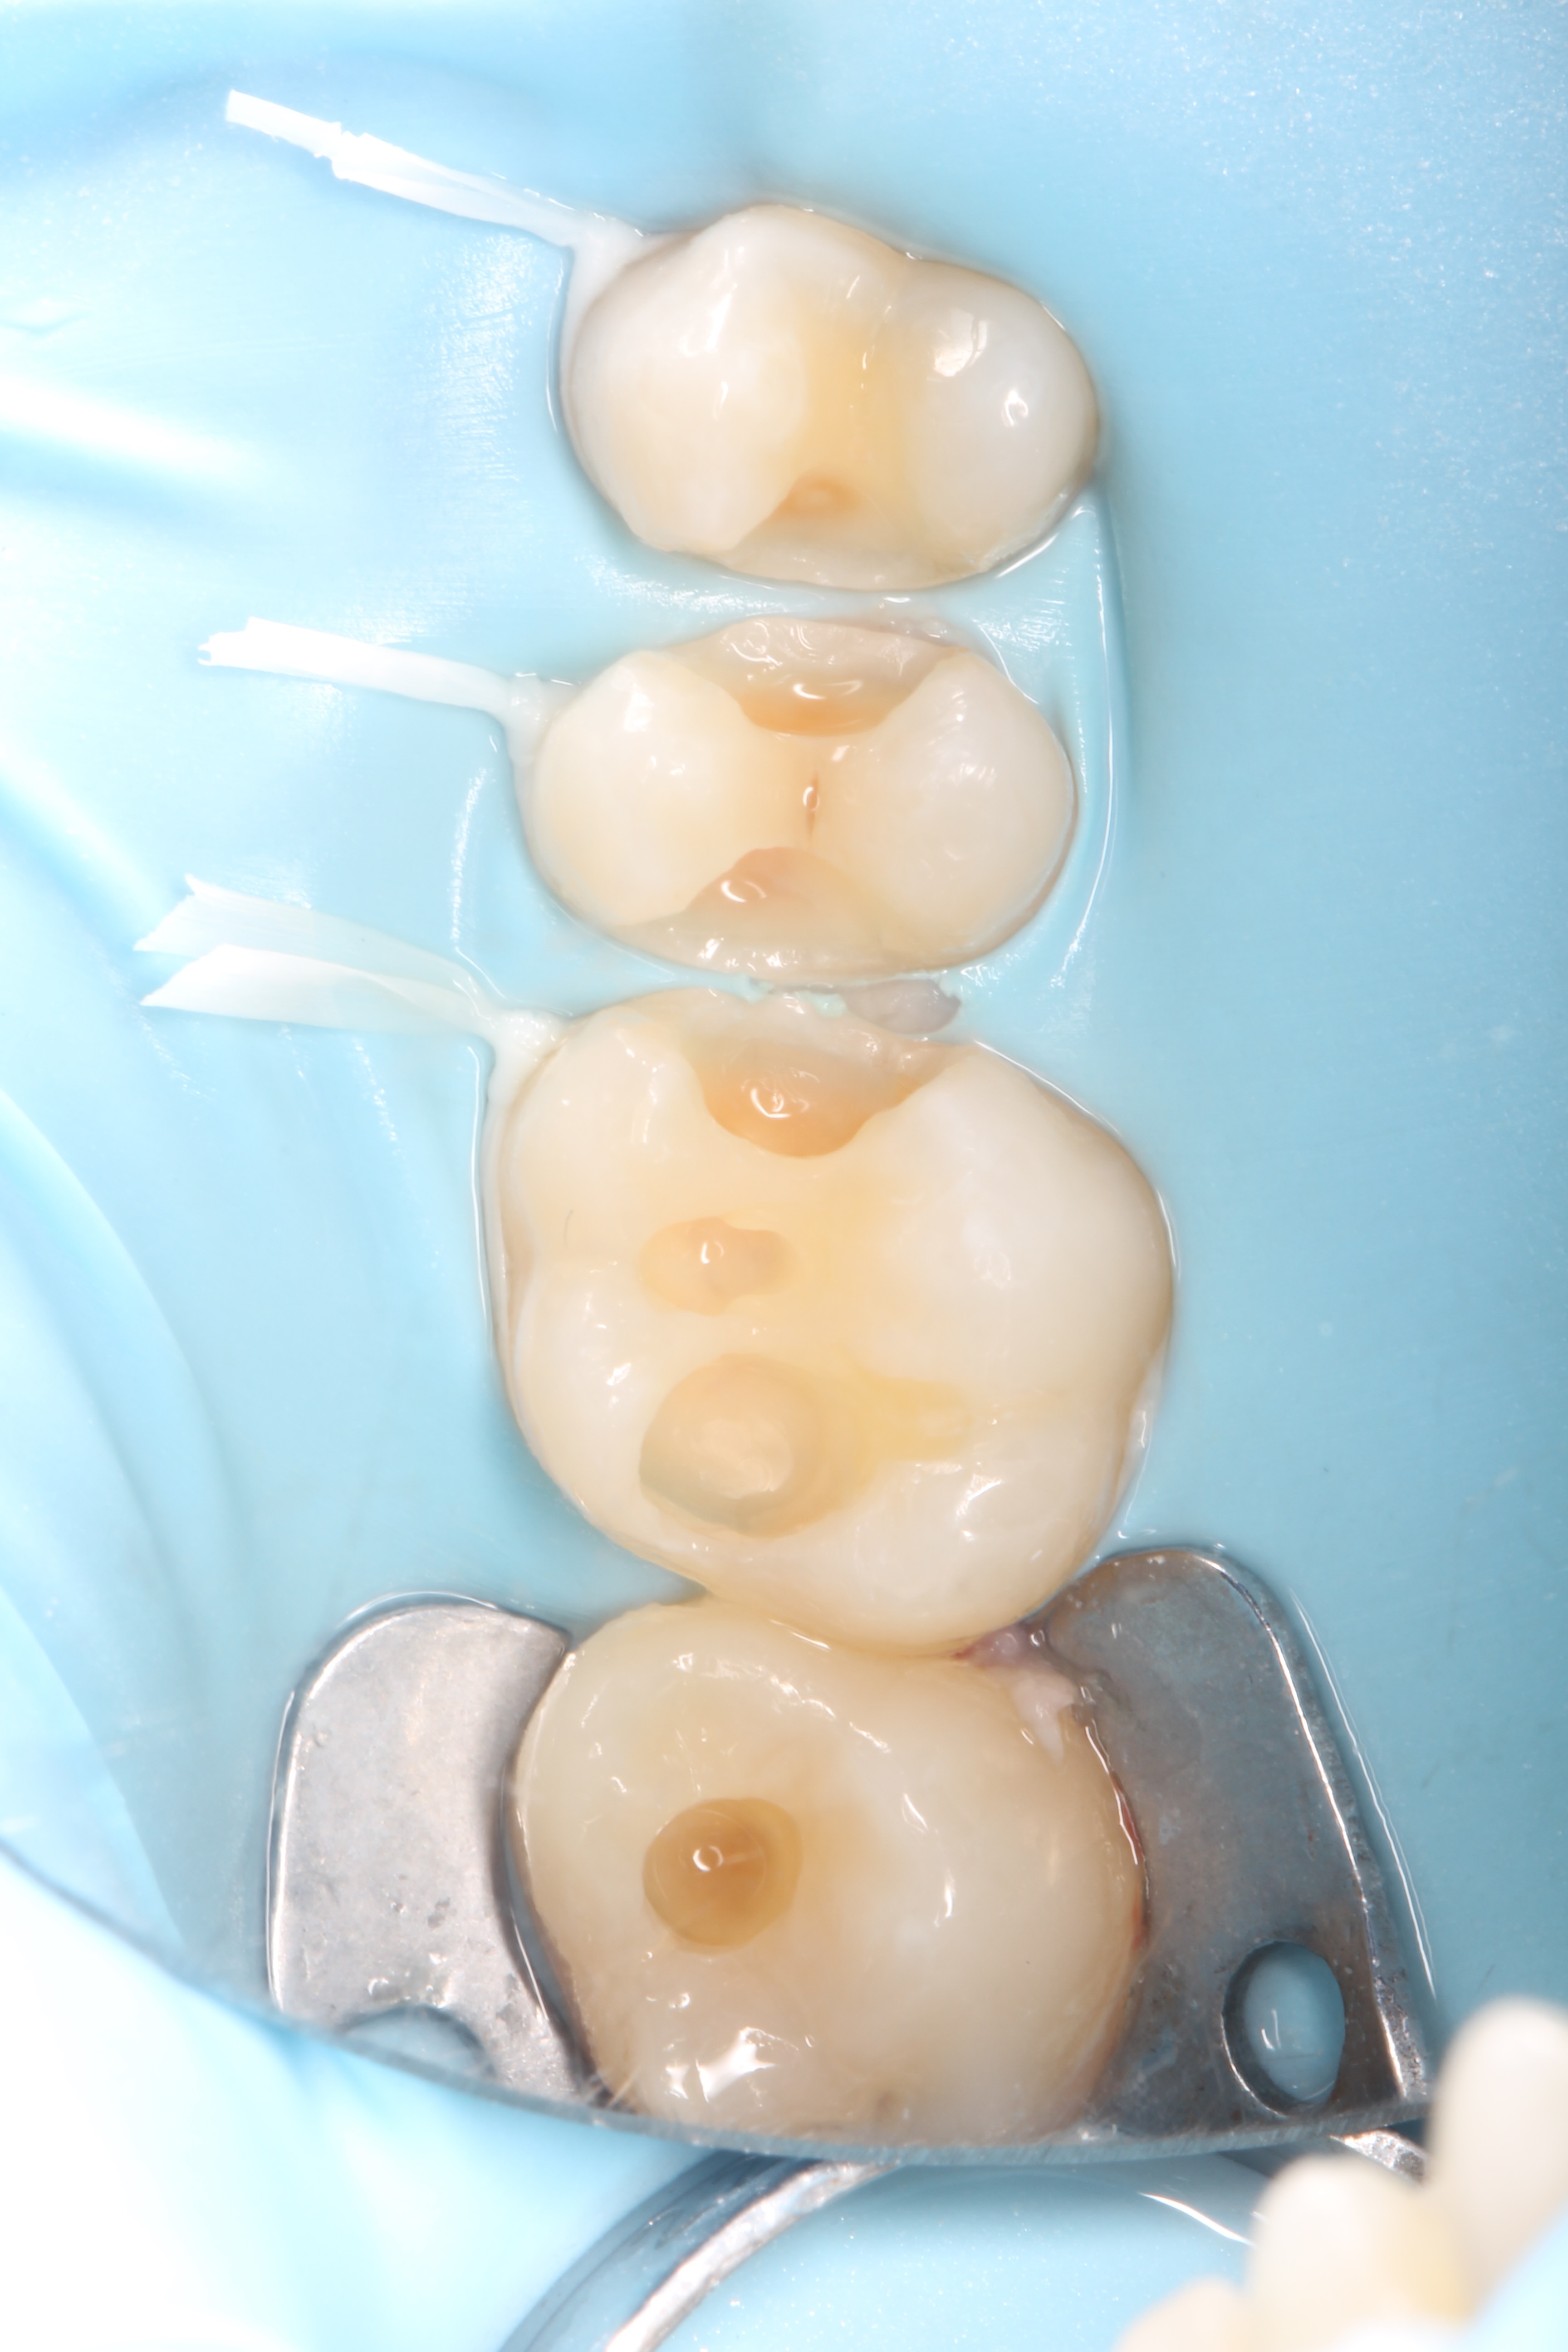

Crowns and onlays by Professor Brian Millar

This course solidified my knowledge and allowed me to practice various cuspal coverage treatments including overlays, onlays and vonlays. I was able to learn about the different preparation techniques and margins required for each indirect material.